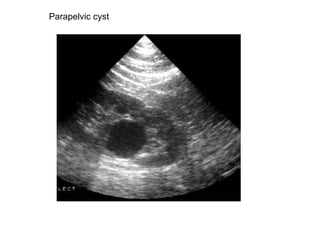

Parapelvic cyst